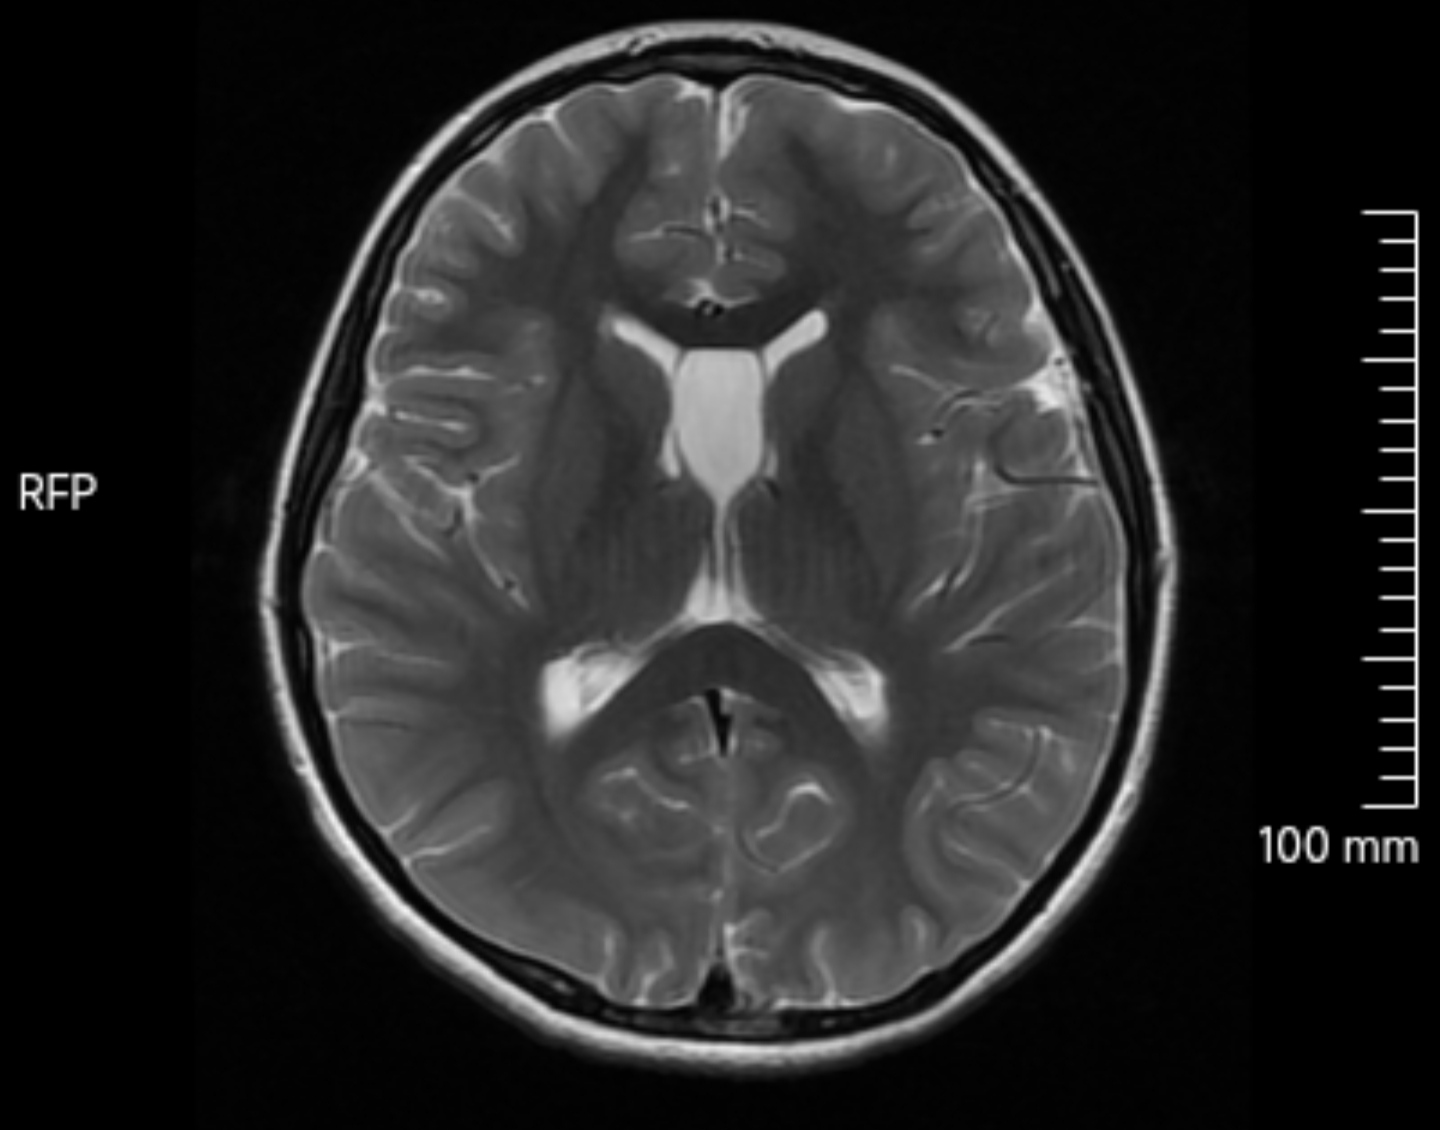

透明隔囊肿